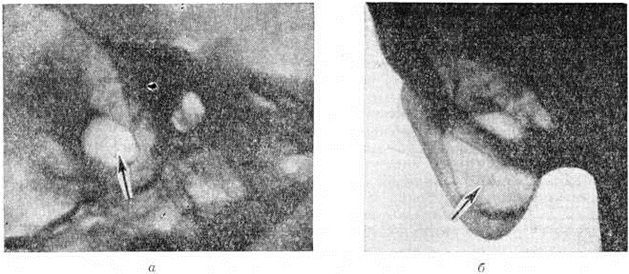

Классическим методом рентгенологическое исследования сосцевидного отростка является предложенная Шюллером (A. Schuller, 1905) рентгенография височной кости в боковой проекции (рисунок 1), а также предложенная Стенверсом (Н. W. Stenvers, 1928) рентгенография сосцевидного отростка в косой проекции (рисунок 2). Рентгенологические картина начальной экссудативной стадии острого Мастоидит характеризуется только затемнением сосцевидных ячеек; симптомы нарушения костной структуры отсутствуют. Резкое понижение воздушности ячеек приводит к снижению естественной контрастности снимка и затрудняет выявление тончайших костных перекладин между ячейками височной кости. В пролиферативно-альтеративной стадии Мастоидит с выраженным разрушением перекладин сосцевидных ячеек на рентгенограмме обнаруживается значительная потеря интенсивности линейных теней перекладин, а местами почти полное их отсутствие. При гнойном расплавлении перекладин и образовании абсцесса в сосцевидном отростке определяется очаг разрежения костной ткани. Очаг костной деструкции некоторое время может сохранять на рентгенограмме трабекулярную структуру, что объясняется наличием сохранившихся ячеек, окружающих полость абсцесса. При образовании субпериостального абсцесса с полным разрушением костной ткани просветление от деструктивного очага становится интенсивным и бесструктурным (рисунок 3). В период сохранения трабекулярности в области абсцесса, особенно небольшого, рентгенологическое распознавание его может представлять значительные трудности. Полость такого абсцесса в хорошо развитом пневматическом сосцевидном отростке ясно видна на томограммах височной кости.

Крупная одиночная ячейка в сосцевидном отростке (относительно редкий анатомический вариант), дающая в норме на рентгенограмме интенсивное просветление, может быть принята за Мастоидит с субпериостальным абсцессом (рисунок 4). Отличить полость субпериостального абсцесса от полости, вызванной холестеатомой в сосцевидном отростке, можно по характеру их границ. Полость субпериостального абсцесса, как правило, не имеет чётких очертаний, свойственных холестеатоме (смотри полный свод знаний). В сомнительных случаях диагностика проводится только путём клинико-рентгенологическое сопоставлений. Верхушечный Мастоидит (абсцесс Бецольда) может быть легко пропущен, если сделать одну боковую рентгенограмму височной кости (рисунок 5, а). При толстой наружной пластинке коркового вещества сосцевидного отростка костный дефект внутренней пластинки на боковом снимке не обнаруживается. На снимке в косой проекции по Стенверсу дефект этой пластинки выявляется чётко (рисунок 5, б). Для распознавания верхушечного Мастоидит очень важен учёт клинические, симптомов, определяющих тактику рентгенолога. Симптом полости рентгенологически нередко обнаруживается и при замаскированных Мастоидит при лечении антибиотиками. Рентгенологические наблюдение показывает, что консервативное лечение Мастоидит при благоприятных исходах ведёт к полной костной регенерации полости абсцесса и восстановлению воздушности сохранившихся ячеек. Серийное послойное рентгенологическое исследование височной кости таких больных указывает на замещение дефекта нормальной костной тканью (рисунок 6, а, б) и перестройку сосцевидного отростка, тип строения которого из распространённого пневматического становится смешанным спонгиозно-пневматическим. Рентгенологические наблюдения указывают на длительность этого процесса (1 — 2 года).